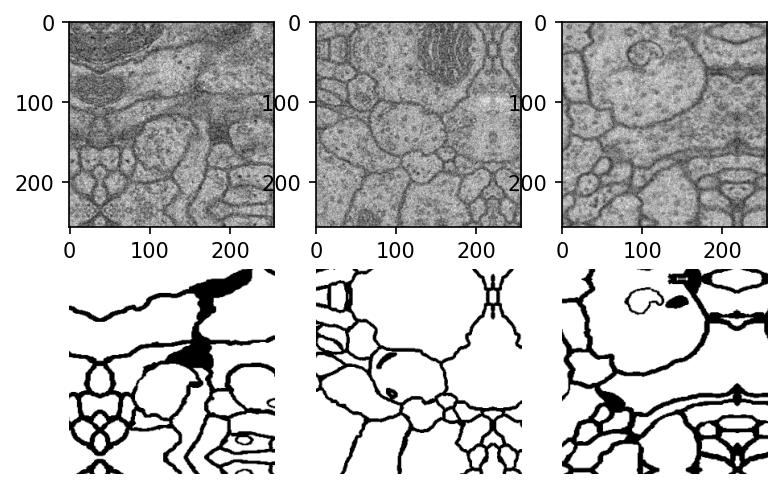

plt.figure(dpi=100) for i in range(3): img, mask = next(my_generator) plt.subplot(2, 3, i + 1) plt.imshow(img[0, :,:,0], cmap="gray") plt.subplot(2, 3, i + 4) plt.imshow(mask[0, :, :, 0], cmap="gray") plt.axis('off') plt.show()オリジナルの細胞画像と塗り分け済み画像が正しく対応づけられた、画像バッチが作成されているのが見て取れます。また端の方で一部反射したような画像になっています。これはImageDataGeneratorで "fill_mode":"reflect"としたため、画像を平行移動した際に生じる空白をreflectモードで補完したためです。

環境はpython3.7、Tensorflow2.1.1を使用しています。画像データ

ISBI challenge 2012(Segmentation of neuronal structures in EM stacks)に載っている細胞の画像データを用いています。ホームページ上から登録を行うことで画像データをダウンロードできます。元の細胞画像と塗り分け済みのデータが入っています。このデータを基にして教師あり学習で自動的に塗り分けを行うために、学習データの整備をしていきます。

画像パッチの作成

オリジナルの画像データは(512, 512)のサイズになっています(上図)。この画像を(256, 256)のサイズに分割します。

plt.figure(dpi=100) for i in range(3): img, mask = next(my_generator) plt.subplot(2, 3, i + 1) plt.imshow(img[0, :,:,0], cmap="gray") plt.subplot(2, 3, i + 4) plt.imshow(mask[0, :, :, 0], cmap="gray") plt.axis('off') plt.show()オリジナルの細胞画像と塗り分け済み画像が正しく対応づけられた、画像パッチが作成されているのが見て取れます。また端の方で一部反射したような画像になっています。これはImageDataGeneratorで "fill_mode":"reflect"としたため、画像を平行移動した際に生じる空白をreflectモードで補完したためです。